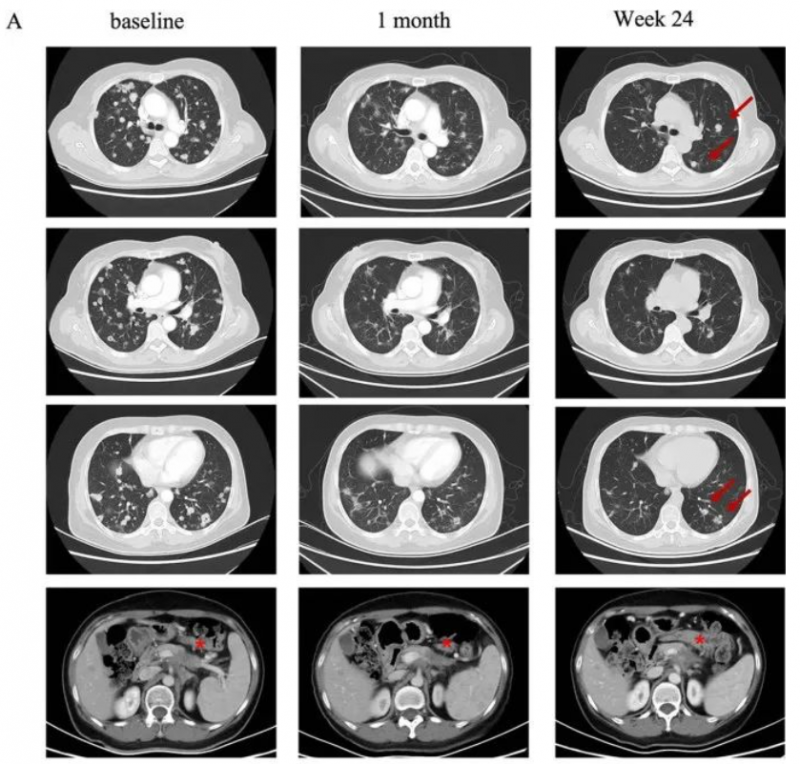

一名58岁的女性胰腺癌患者,伴有肺及淋巴结转移。该患者先后经历一线白蛋白紫杉醇联合吉西他滨和二线伊立替康联合5-氟脲嘧啶治疗后失败。经检测其Claudin18.2表达为2+/70%后入组CT041临床试验。

在进行氟达拉滨、环磷酰胺、白蛋白紫杉醇方案清淋预处理后,患者于2021年9月接受CT041细胞输注。输注后患者出现2级细胞因子释放综合征(CRS),在接受托珠单抗后恢复。根据RECIST v1.1标准,患者肿瘤评估达到部分缓解(PR),肺部转移灶明显缩小。